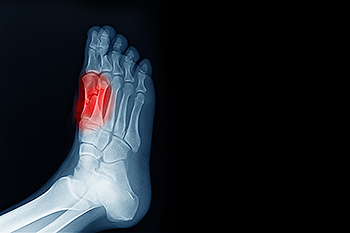

A condition known as sesamoiditis occurs when tissues that embed the two tiny sesamoid bones just under the base of the big toe become inflamed. Sesamoiditis is considered to be an overuse injury, caused when pressure is repeatedly put on the ball of the foot, especially when flexing the big toe. As a result, this injury is common among runners, football players, dancers and basketball players. Treatments vary for sesamoiditis, and experts find that a combination of them works best. Included are eliminating the activities that cause the overuse, taking pain medication, and performing certain exercises. Wearing shoes that fit properly is recommended, and wearing high-heels or any shoes that force the weight onto the ball of the foot should be avoided. In some cases, depending on the severity of the sesamoiditis, cortisone injections can be effective in reducing the symptoms of pain, swelling, and difficulty bearing weight. Gel and foam orthotics are often used to reduce the pain. To find out more about treating sesamoiditis, please consult a podiatrist.

Sesamoiditis is a condition of the foot that affects the ball of the foot. It is more common in younger people than it is in older people. It can also occur with people who have begun a new exercise program, since their bodies are adjusting to the new physical regimen. Pain may also be caused by the inflammation of tendons surrounding the bones. It is important to seek treatment in its early stages because if you ignore the pain, this condition can lead to more serious problems such as severe irritation and bone fractures.